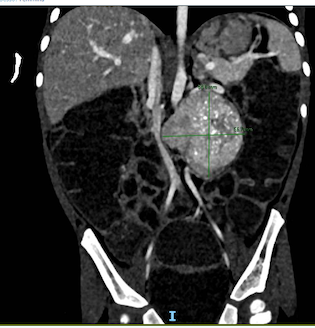

Nelle settimane successive, per persistenza della diarrea e sviluppo di distensione e dolore addominale ingravescenti e calo ponderale, veniva effettuata una radiografia del transito gastrointestinale per escludere anomalie anatomiche maggiori e veniva ripetuta un’ecografia addominale. Quest’ultima mostrava una neoformazione ovalare di circa 48x40x58 mm in sede retroperitoneale con segni di vascolarizzazione. Le immagini di RM e TC (Figura) associate al riscontro di catecolamine urinarie elevate (acido omovanillico e acido vanilmandelico, rispettivamente 430 e 70 μg/mg di creatinina con vn < 18,6 μg/mg di creatinina e < 11,8 μg/mg di creatinina) risultavano compatibili con un quadro di neuroblastoma (NB), confermato in seguito ad agobiopsia percutanea ecoguidata.